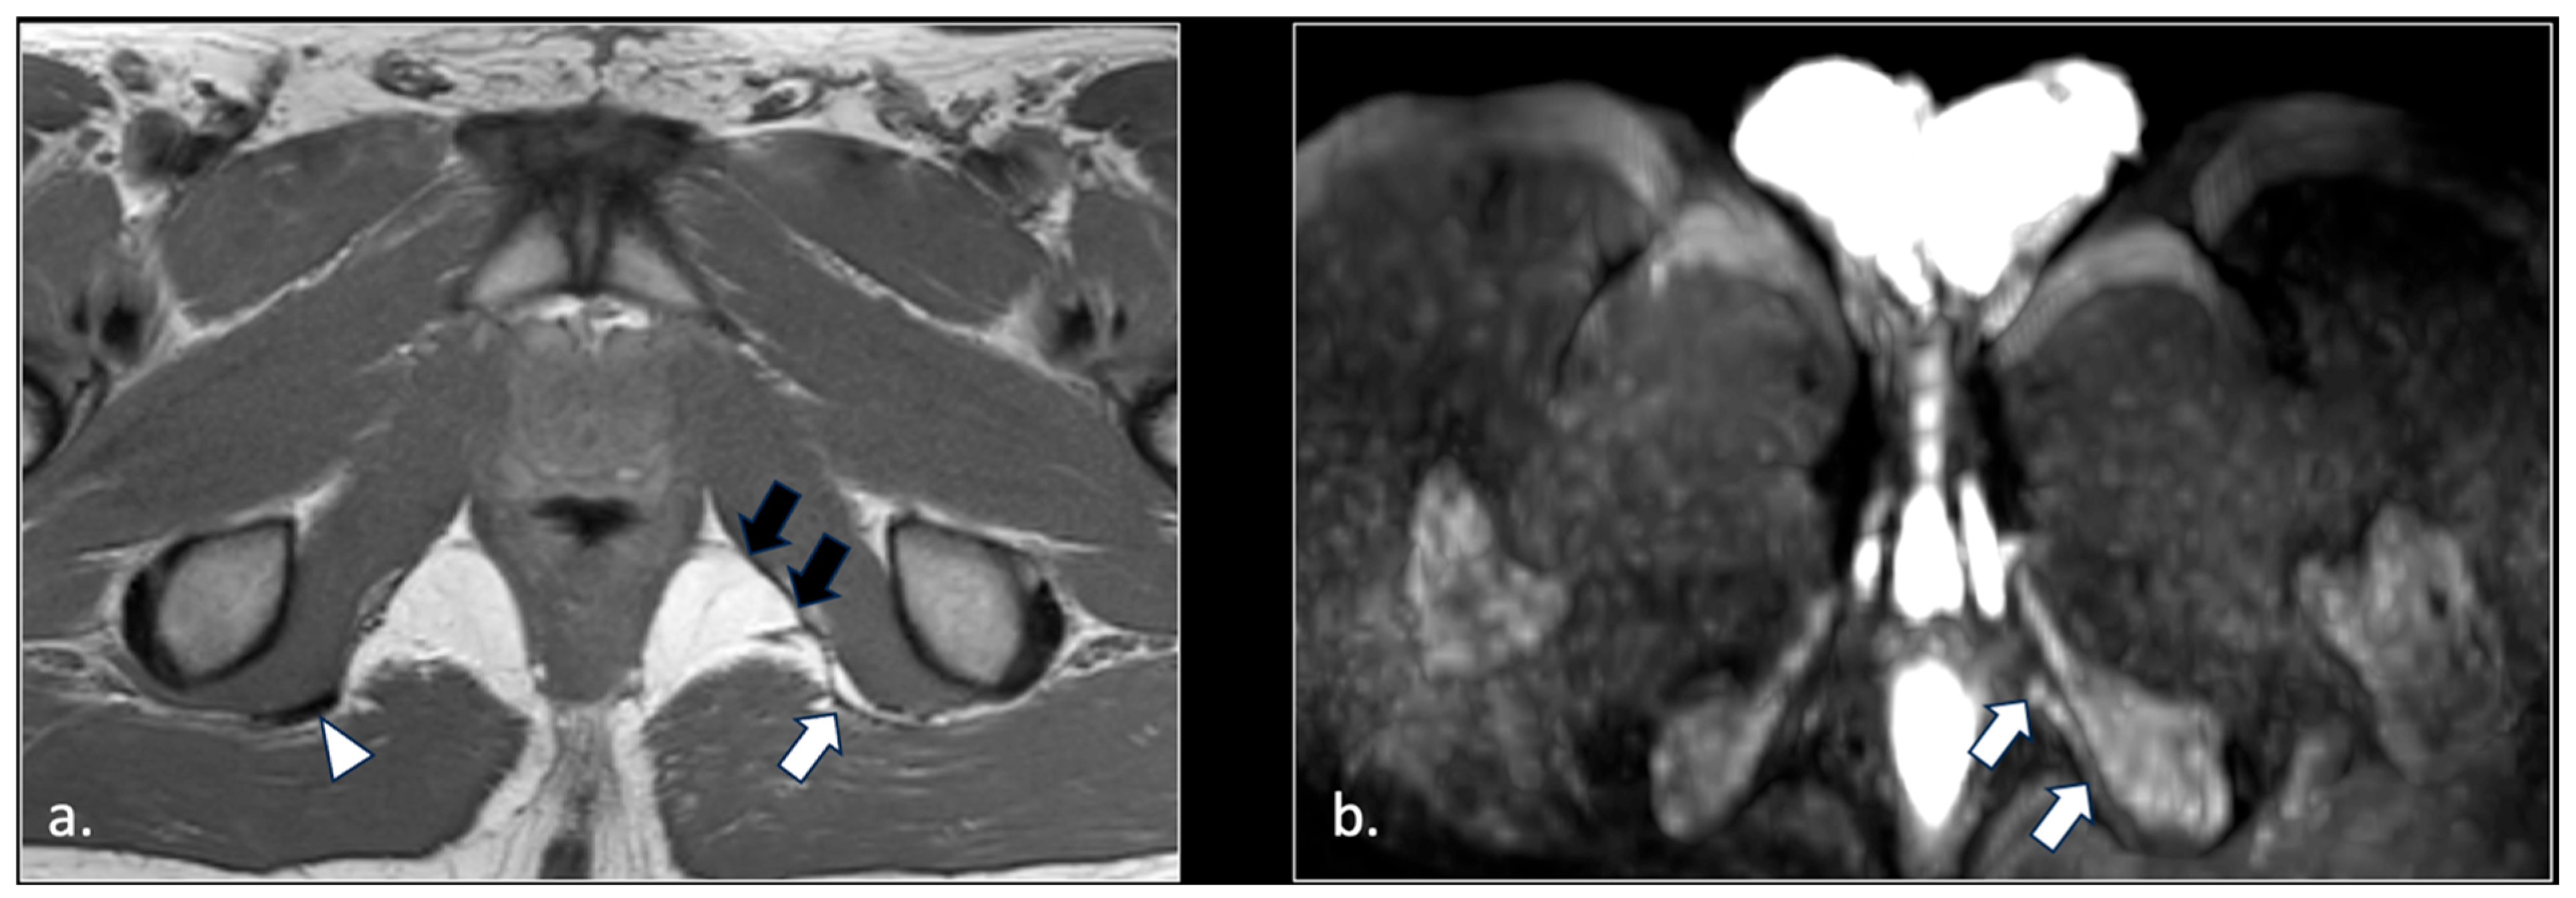

- Unilateral or bilateral lesions of the sacrotuberous and/or sacrospinous ligaments (interligamentous space) (5 patients);

- Unilateral rupture of puborectal and/or pubococcygeal muscle (4 patients);

- Perineal fibrosis involving Alcok’s canal (4 patients);

- Varices of the pudendal vein in the Alcock canals (2 patients).